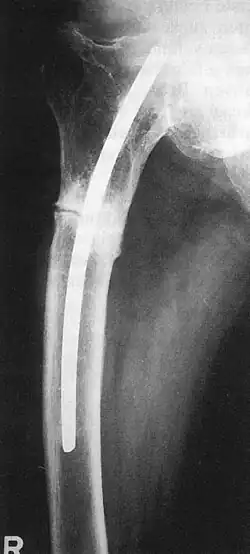

Küntscher befasste sich während dieser Zeit mit Bau und Funktion des Knochengewebes; in Experimenten für seine Habilitationsschrift stellte er erstmals den Kraftfluss in Röhrenknochen dar und erforschte die Bruchheilung und Kallusbildung. Mit Ernst Pohl als kongenialem „Handwerker“ inaugurierte Küntscher die Technik der intramedullären Bolzung zur Marknagelung, wobei er sich nach eigenem Bekunden an Vorarbeiten der (weithin unbekannt gebliebenen) Mediziner Oskar Müller-Meernach und Georg Schöne orientierte.1939 führte er erstmalig seine Technik der Marknagelung an einem menschlichen Schaftbruch des Oberschenkelknochens durch, nachdem ein Ingenieur aus großer Höhe in ein Trockendock einer Kieler Werft gestürzt war und sich dabei multiple Brüche der Beckens und der Beine zugezogen hatte.[7] Die „Innenschiene für Röhrenknochen“ ließ er sich kurz darauf, am 17. Dezember 1939, beim Reichspatentamt patentieren. Im März 1940 berichtet er dann erstmals auf dem 68. Chirurgenkongress in Berlin von seiner Technik, traf jedoch auf Ablehnung. Allein sein Chef Fischer sprang ihm so moderat wie entschieden bei, so dass die Technik in der Folge in Kiel weiter angewandt und in der Folge verfeinert wurde. Erst während des Zweiten Weltkrieges kam es zu einer schnellen Verbreitung seiner Technik. Auf dem Chirurgenkongress hatte Küntscher einen Marknagel mit V-förmigem Profil vorgestellt, dem im selben Jahr ein geschlitzter Marknagel mit kleeblattförmigem Querschnitt[8] folgte. In das Jahr 1940 fällt auch seine Erfindung des sog. Gammanagels, der – immer weiter vervollkommnet – bis heute zum Standardrepertoire bei der Behandlung hüftgelenksnaher („pertrochantärer“) Oberschenkelbrüche zählt.[7]

- Rüdiger Döhler, Dirk Hasselhof, Friedrich Hennig: Femurnagelung von Küntscher – eine 74-jährige Krankengeschichte. Der Chirurg 62 (1991), S. 761–762.